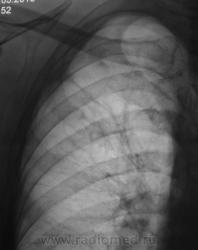

Какая-то фиброзно-кистозная дегенерация легочной ткани в/д правого л-го. Вероятно, приобретенная.

Остаточные буллёзно-фиброзные изменения излеченного туберкулеза легких?